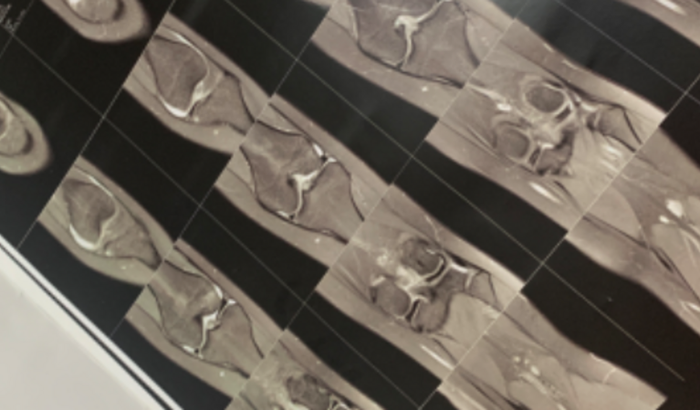

Para minha cirurgia no joelho

Enquanto treinava para ir realizar meu sonho de jogar em um time, acabei rompendo o LCA. Me forçando a parar com meu sonho e minha maior felicidade, que era jogar futebol. ver tudo

Enquanto treinava para ir realizar meu sonho de jogar em um time, acabei rompendo o LCA. Me forçando a parar com meu sonho e minha maior felicidade, que era jogar futebol.